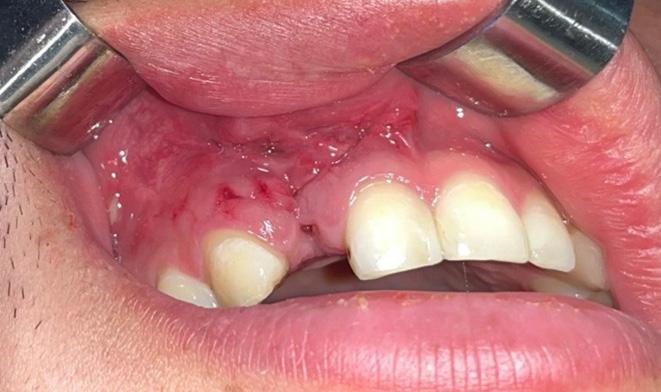

Issuu converts static files into: digital portfolios, online yearbooks, online catalogs, digital photo albums and more. Sign up and create your flipbook.